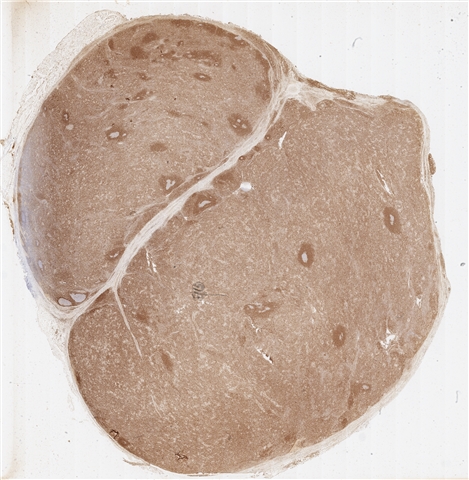

案例3 (6862)

性别:       年龄:65

患者详情: 患者3月余前在当地社区卫生服务中心体检发现血肌酐升高(109.8umo/L),无明显尿量减少,无颜面下肢浮肿无腰酸腰痛,无肉眼血尿,无关节疼痛,无皮疹红斑,开始未重枧及进一步诊治。10余天前患者到中山医院复查生化提示“肌酐200umol/L、尿素7.3mmol/L、尿酸637umol/L、白蛋白34g/L、球蛋白66g/L、蛋白电泳β15.0%、蛋白电泳Y42.6%”,同时其它检查提示“血lgG4 54.20g/L”。 CT:纵隔及双侧腋下多发肿大淋巴结,肺动脉干稍増粗,主动脉硬化,扫及双肾饱满,后腹膜发淋巴结。 PET-T:全身多区域淋巴结肿大、双侧泪腺、双侧颌下腺及胰腺体尾部饱满、双肾实质肿胀,左侧头皮局部增厚,伴FDG代谢增高,鼻咽顶后壁及前列腺腺体FDG代谢增高,上述病灶首先考虑IgG4相关性疾病所致可能,建议暖股沟淋巴结活检病理明确除外淋巴瘤。

大体所见: 结节一枚3*3*2cmA-C。

医院: 上海交通大学医学院附属仁济医院